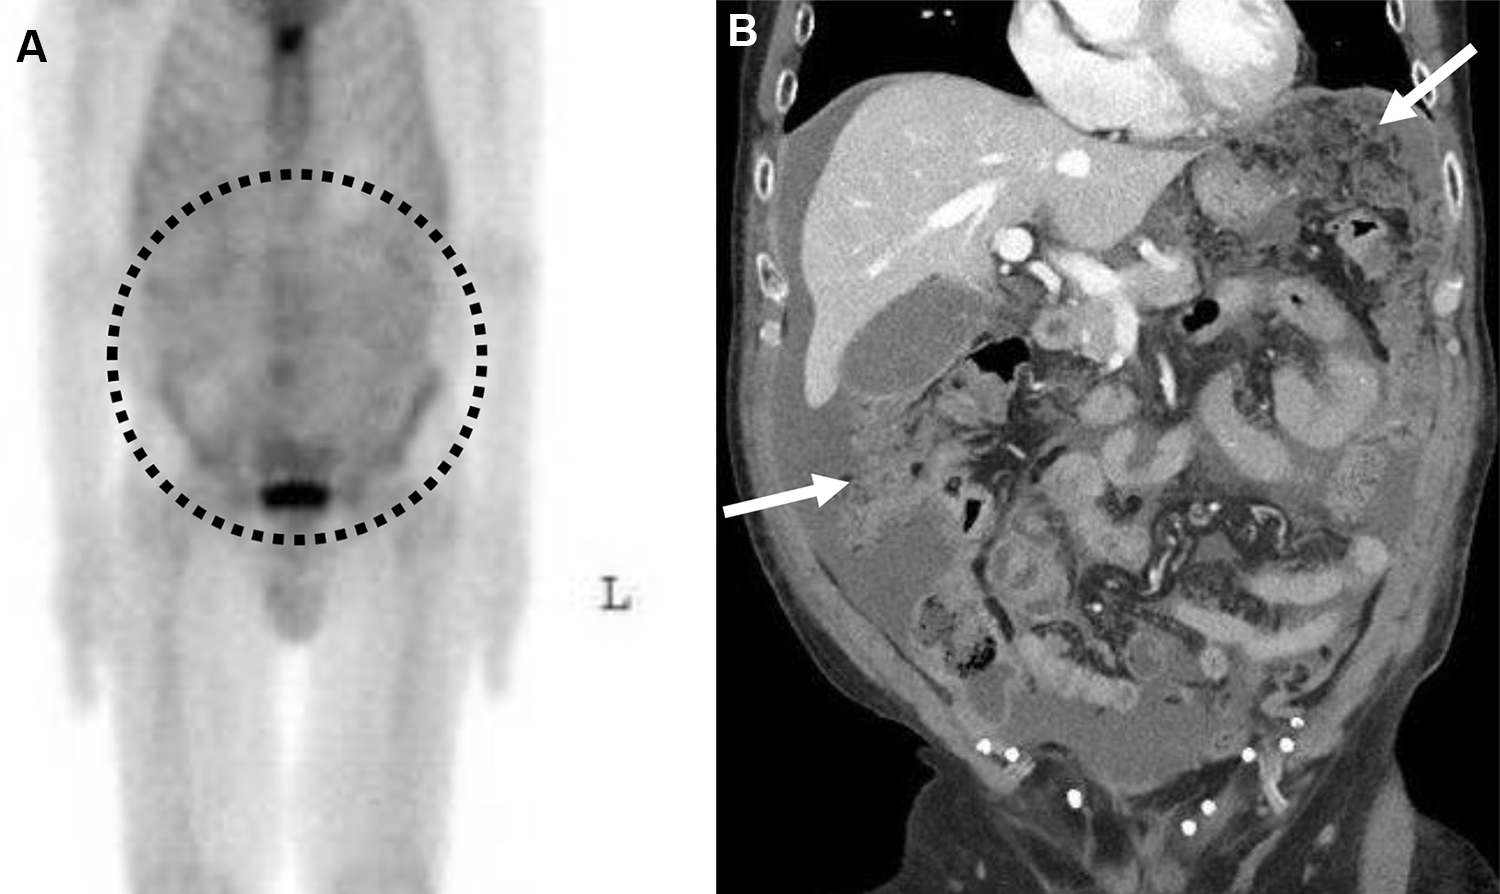

Carcinosi peritoneale e ascite in un uomo di 58 anni con carcinoma a cellule renali metastatico.

La scintigrafia ossea total body rileva un’anomala captazione extra-ossea a livello addominale. La distribuzione “a chiazze” (patchy) e diffusa del radiotracciante riflette il suo accumulo all’interno della cavità peritoneale.

L’imaging TC conferma la natura del reperto scintigrafico, documentando la presenza di ascite neoplastica e impianti nodulari solidi (carcinosi) a carico del mesentere e dell’omento.

Analogamente a quanto avviene per i versamenti pleurici, il tecnezio difosfonato può diffondere e accumularsi nei fluidi ascitici o all’interno dei noduli di carcinosi peritoneale. Questo fenomeno secondario è spesso legato all’aumentata permeabilità vascolare locale o alla presenza di microcalcificazioni nel tessuto tumorale.